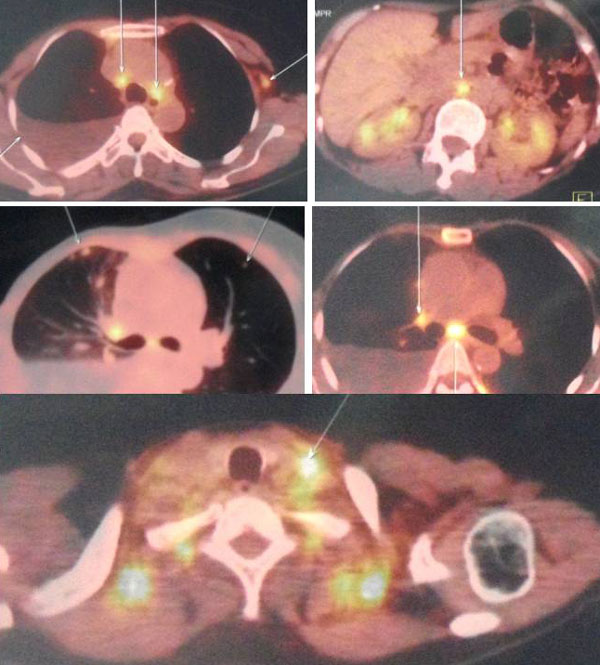

Ria came back to the same private hospital in Penang where she had her surgery. She was referred to the lung specialist. A CT was done and showed the following:

- There is a 5.5 x 5.1 x 3.5 cm mass in the manubrium sterni with an extension of the mass into the prevascular space of the mediastinum.

- There is moderate to large right pleural effusion (fluid in the lung).

- Collapse-consolidation of right lower lobe.

- Right and left main pulmonary arteries and their lobar branches are consistent with pulmonary embolism (PE).

From the pictures above, her breast cancer must have spread to her lungs, bone and liver. In addition she suffered DVT of the right leg. The doctor wanted Ria to be admitted into the hospital right away, to treat her DVT. She also refused.